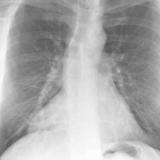

Case 4a

Peric effusion

Date: 03/17/2004

Views: 2850